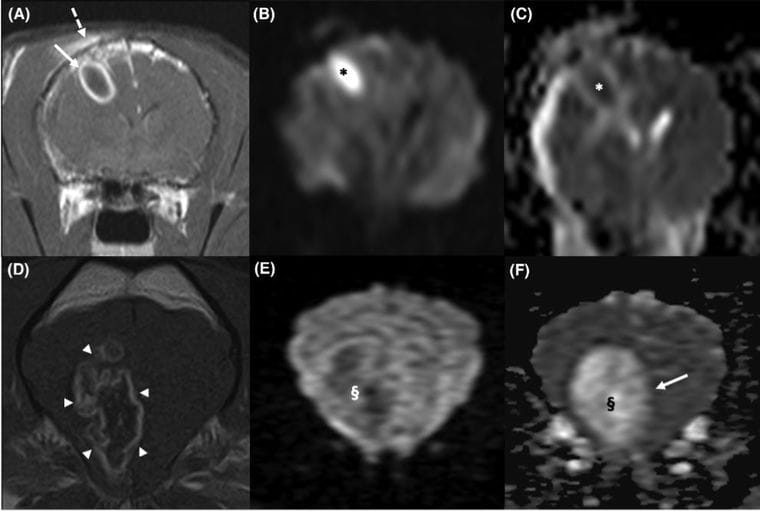

A–C, 1.5 T, transverse T1W FSE TR 500, TE 13 and transverse DWI/ADC TR 4233, TE 110, B value 1000) A 9-year-old maleneutered DSH cat with a right parietal lobe abscess secondary to a bite wound. An even, well-defined ring-enhancing lesion with a hypointensecenter (arrow) is visible on the T1 postcontrast sequence (A); right temporal myopathy and a calvarial defect are also visible (dashed arrow). On thetransverse DWI (B), the central portion of the abscess is strongly hyperintense to normal brain parenchyma (black asterisk), while it shows lowvalues (white asterisk) on the ADC map (C), consistent with restriction to diffusion. D–F, 1.5 T, transverse T1W FSE TR 465, TE 11 and transverseDWI/ADC TR 4288, TE 94, B value 1000) 5-year-old male French Bulldog with ring-enhancing glioma of the right frontoparietal lobe. The T1Wpostcontrast sequence shows an unevenly marginated ring-enhancing glioma (arrowheads) (D). On the transverse DWI (E), the central portion ofthe lesion is hypointense (white §) to normal brain parenchyma, while on the ADC map (F), it shows a high signal (black §), consistent withunrestricted diffusion. Note the difference between the even enhancing capsule of the brain abscess (A) compared to the unevenly marginatedring-enhancing glioma (D)